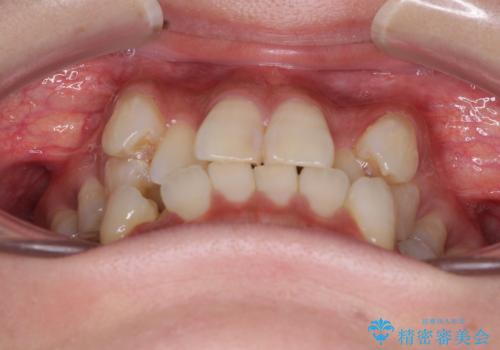

- 八重歯や前歯のデコボコを気にして来院された患者様です。

目立たない装置を希望されたので、上顎が裏側装置のハーフリンガルを選択し、上下左右の小臼歯(計4歯)を抜歯して矯正治療を行うこととしました。

デコボコが強い一方で出っ歯ではなかったため、抜歯したスペースを容易に閉じることができ、短期間での治療となりました。